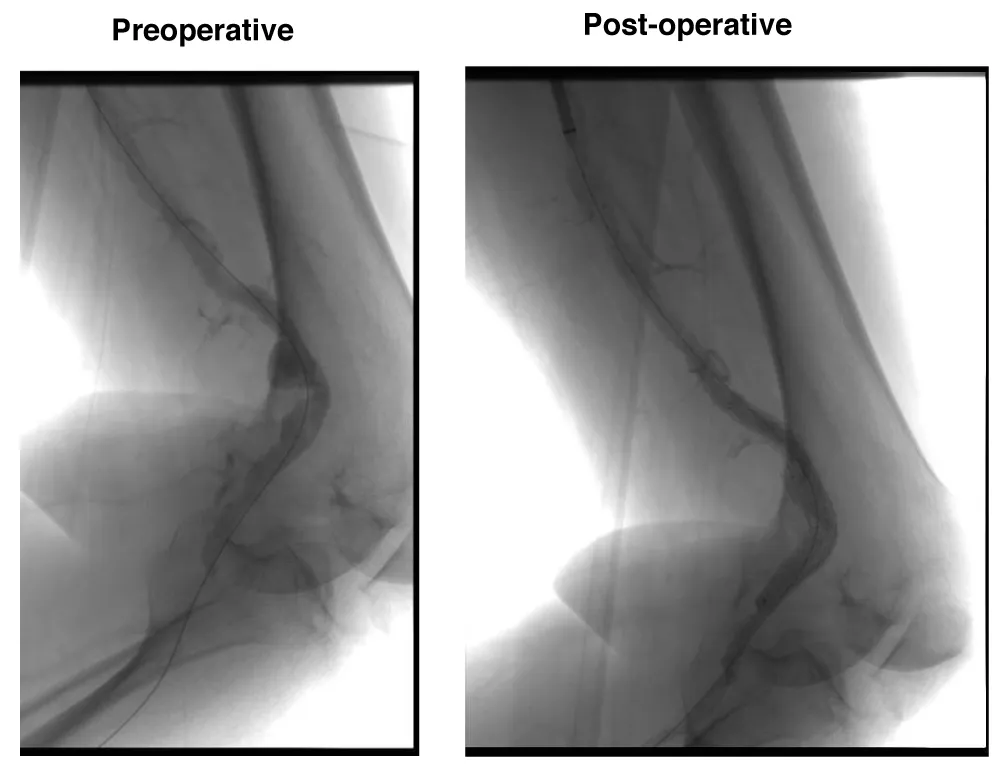

A male patient, 74 years old, with arterial hypertension and diabetes was admitted with right Lower limb rest pain due to acute arterial occlusion. The patient underwent AngioCT scan which demonstrated a 26 mm popliteal artery aneurysm thrombosis. The patient was submitted to endovascular surgery with popliteal implant of endoprosthesis Wrapsody® 12x80 mm at distal neck and Wrapsody 12x80 mm at proximal neck, followed by catheter balloon dilatation, after proper intra-arterial thrombolysis (Figure 3). The patient was discharged from the hospital on the first day post-operative with Rivaroxaban 20mg/day and a 2-month follow-up showed endoprosthesis patency with complete resolution of the previous symptoms.

Figure 3: Endovascular thrombolysis and stenting of a 74-year-old male with acute thrombosed 26 mm popliteal artery aneurysm: Preoperative CT angiography reveals occlusion and aneurysmal dilation. Postoperative image confirms successful thrombolysis and exclusion with two Wrapsody® stents (12×80 mm each), with reestablished distal perfusion.